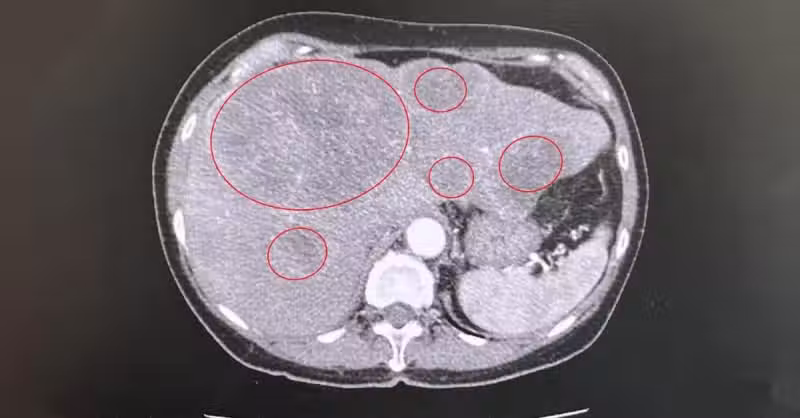

而陳周誠也透過大腸鏡檢查診斷,婦女直腸上段三分之一處有一顆約7公分大的癌腫瘤,並轉移至肝臟,腹部電腦斷層掃描也看見肝臟布滿大大小小,由1公分到6.5公分不等的直腸癌轉移腫瘤。